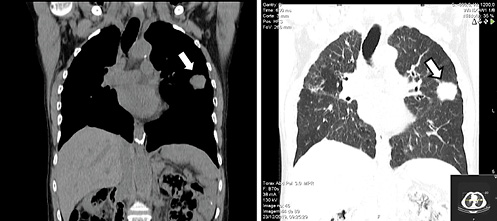

Thoracic, abdominal, and pelvic computed tomography (CT) without contrast (due to a known history of allergy) was performed. The images displayed many nodular lesions in both lungs, the largest located in the superior left lobe with a size of 31 × 34 mm (Fig. 3); biopsy revealed it as compatible with additional areas of MALT lymphoma involvement. There were no other lesions observed in the abdominal or pelvic plans including nodal involvement areas. Bone marrow biopsy was performed and showed no signs of disease infiltration. These areas of involvement classified this patient’s lymphoma as a stage IV disease according to the Lugano staging system [5].

Fig. 3 Thoracic CT scan showing the larger pulmonary lesion in the superior left lobe (white arrows).